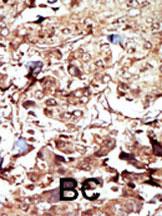

Formalin-fixed and paraffin-embedded human cancer tissue reacted with the primary antibody, which was peroxidase-conjugated to the secondary antibody, followed by AEC staining. This data demonstrates the use of this antibody for immunohistochemistry; clinical relevance has not been evaluated. BC = breast carcinoma; HC = hepatocarcinoma.